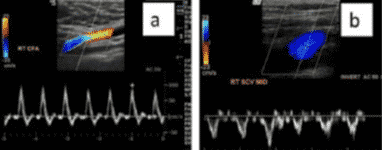

En el caso de existir dudas, el método más fiable para diferenciarlas seria la realización de un Doppler pulsado donde las venas se representan como una onda bifásica y a veces una retrograda de baja velocidad; mientras que la arteria presenta un flujo fundamentalmente sistólico de alta velocidad.

En lo que a la técnica se refiere, también se utiliza la sonda lineal de alta frecuencia. En este caso es preferible el uso de Doppler a color, útil también para determinar permeabilidad, aunque también puede emplearse el modo 2D.

La ventaja de contar con Doppler a color es que este modo aporta información sobre la existencia y movimiento del flujo sanguíneo, siendo posible localizar regiones con flujo anormal. Queda representado de la siguiente forma:

- Color rojo: flujo que se acerca al transductor.

- Color azul: flujo que se aleja del transductor.

En la detección de trombos se puede observar una imagen ecogénica heterogénea que ocupa total o parcialmente la luz venosa y se considera un signo prácticamente patognomónico la imposibilidad de comprimir la luz vascular por completo. Además, si utilizamos Doppler a color aplicado sobre la luz vascular se apreciará ausencia de flujo o algún defecto de repleción.